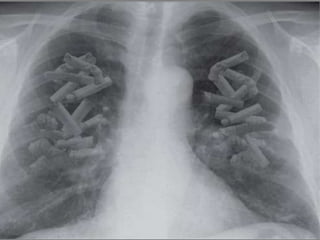

Pulmão normal Pulmão de fumante

Câncer

de

pulmão

90% dos casos

de Câncer de

pulmão são

em fumantes

O Câncer de

pulmão é o que

mais mata,

entre homens

e mulheres

Tabagista pesado

(> 2 maços/dia)

tem risco 30x maior

de câncer de pulmão

que o não-fumante

Câncer de pulmão:

Aspecto macroscópico